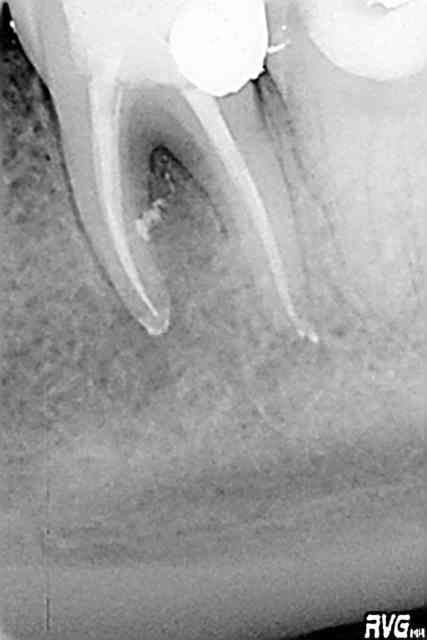

hallboy

04/05/2009 à 17h00

avec du 45.

Mc Spadden pur. Finition au F2

pour faire un coucou a Tonio ;)